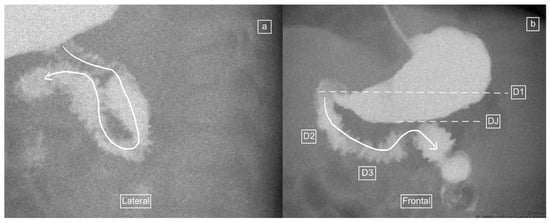

Figure 2.

(a–c): Representative images captured during an UGIS in a 3-month-old boy demonstrating duodenum redundum on the frontal and lateral views. (a) Frontal view demonstrates redundancy of the duodenal loop which instead of having a C-loop configuration now has a W-loop configuration (white line) and a normal position of the duodeno-jejunal flexure (immediately distal to the end of the arrowhead). (b) Early and (c) later lateral views captured prior to the frontal view in (a) demonstrate a descending staircase configuration of D1 and D2 oriented posteriorly, after which the duodenum ascends in the retroperitoneal position, leading up to the duodeno-jejunal flexure in the expected normal position at the same height as D1, before coursing anteriorly.

Figure 3.

(a–d): Representative images captured during an UGIS in a 49-day-old boy demonstrating duodenum redundum on the frontal and lateral views, with the order of images representing the order that the images were captured through multiple repositioning maneuvers. (a) Lateral view demonstrating the descending staircase sign oriented posteriorly from D1 and involving D2. (b) Frontal view demonstrating the W-loop configuration of duodenum redundum made up here by D2 and D3. (c) Repositioning in the lateral view demonstrates the posterior position of D3 inferiorly and that the ascending D4 remains posterior. (d) Return to the frontal position now demonstrates the contrast outlining the duodeno-jejunal flexure (DJ) just slightly inferior to D1 and to the left of the spine—considered within the normal range allowing for patient positioning.

Figure 4.

(a,b): Representative images captured during an UGIS in a 2-month-old boy demonstrating duodenum redundum on the lateral and frontal views. (a) Lateral view demonstrates a descending staircase configuration of D1 and D2 oriented posteriorly, after which the duodenum remains (D3) and ascends (D4) in the retroperitoneal position, leading towards the duodeno-jejunal junction (not shown here). (b) Frontal view demonstrates redundancy of the duodenal loop which, instead of having a C-loop configuration, has a W-loop configuration, made up of D2, D3 and D4 (white line) and a normal position of the duodeno-jejunal flexure (DJ).